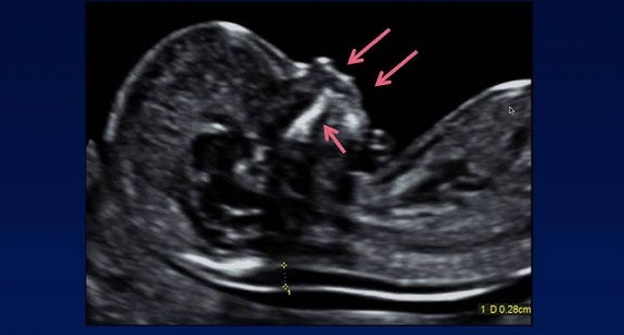

Obstetric Ultrasound Techniques

Gynecological Ultrasound Applications